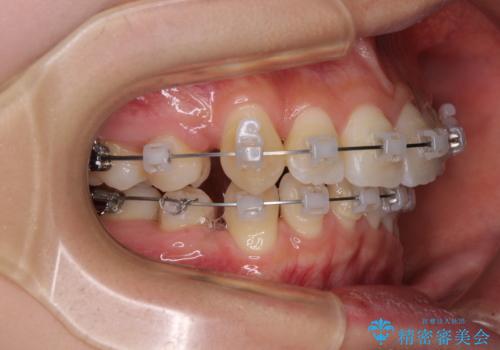

- 矯正装置

- クリアブラケット

- 1年5ヶ月

- 前歯の叢生と八重歯を気にして来院された患者様です。

叢生が強く、奥歯の咬合も左右差が大きかったため、上下左右4本を抜歯して、ワイヤー矯正を行うこととしました。

20歳前後と年齢が若かったため、非常にスムーズに歯列が整い、1年半をかけずに治療を終えることができました。